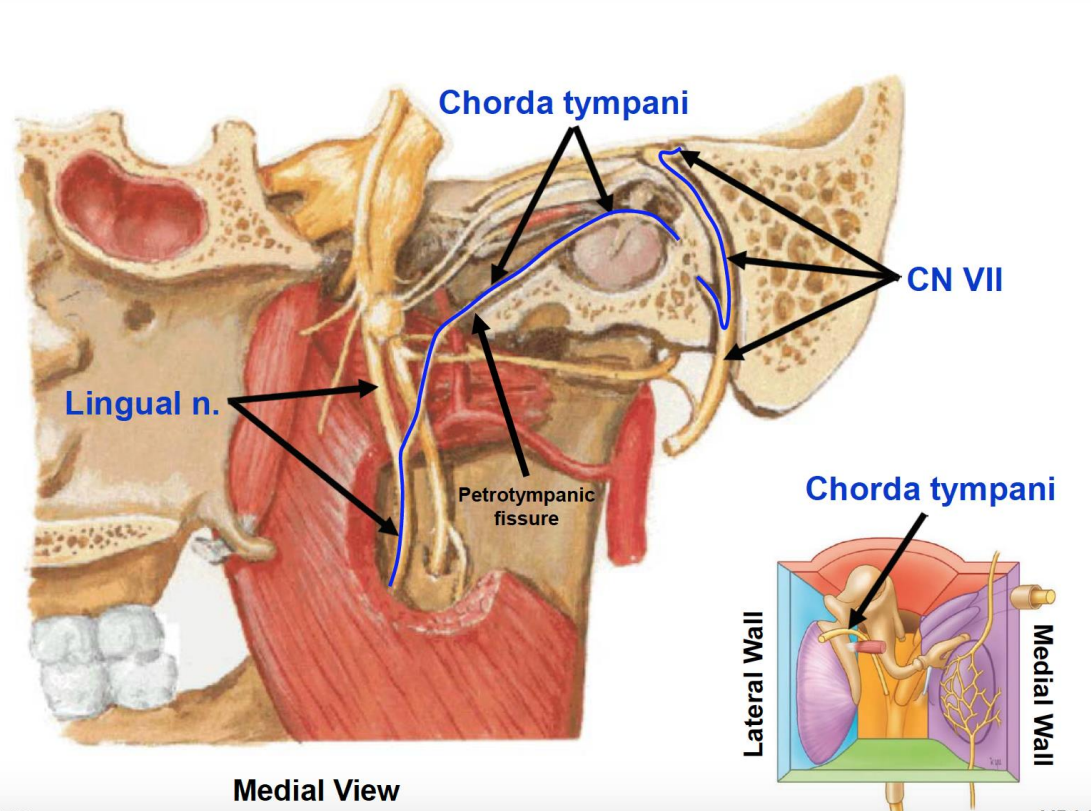

Chorda Tympanic n.(Parasymphysis)

- 支配前味覺

- Submandibular, Sublingual g.

- Petrotympanic fissure